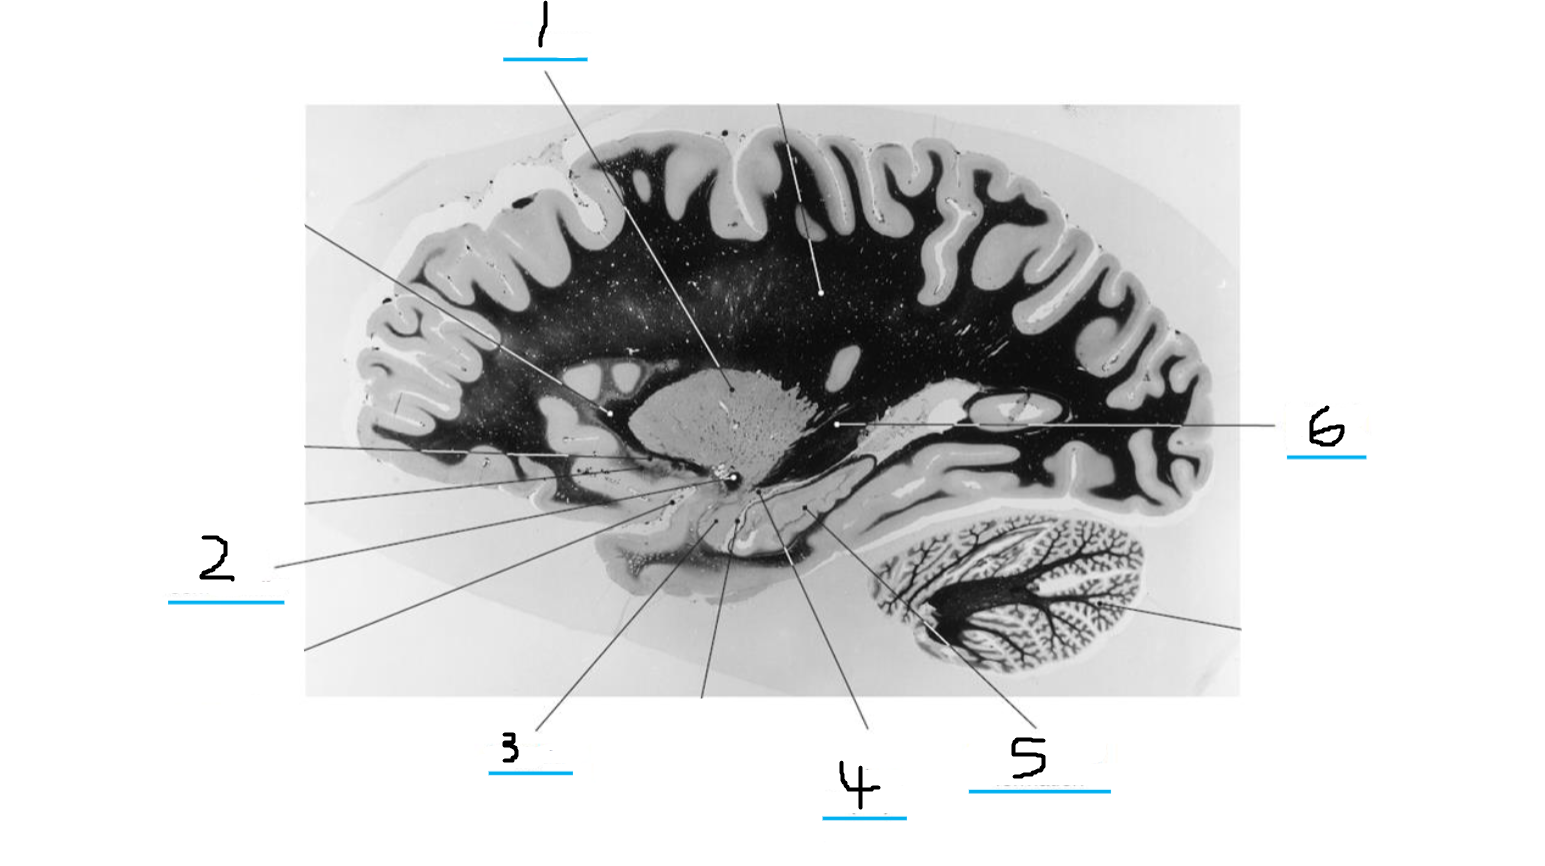

#3 and #16 are the:

Thalamus

#4 is the:

Hypothalamus

#5 and #9 is the:

Hippocampus

#6 is the:

Crus Cerebri

#7 is the:

Basilar Pons

#8 is the:

Mammillary Body

#10 is the:

Caudate

#11 is the:

Third Ventricle

#12 is the:

Globus Pallidus

#13 is the:

Insula

#14 is the

Putamen

#15 is the:

Internal Capsule

#17 is the:

#18 is the:

Lateral Ventricle

#19 is the:

Corpus Callosum